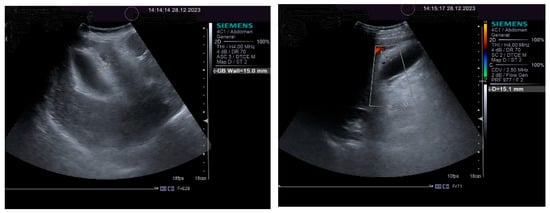

The impressive thickening of the gallbladder wall is illustrated in Figure 3.

The pulsed Doppler ultrasound revealed a patency of the main portal vein as well as of the left and right portal branches and decreased, demodulated hepatopetal portal venous flow, with mildly decreased respiratory variability in the amplitude of the portal vein flow. The Dopler aspects of the liver and spleen are illustrated in Figure 4.

An important role in the imaging diagnostic approach of SOS/VOD is played by ultrasonography. According to some studies, it seems that ascites and gallbladder wall edema represent independent predictors in SOS/VOD diagnosis. Some authors reported that the thickness of the gallbladder wall correlated well with the HVPG. This particular aspect of the markedly thickened GB wall was also observed in the presented patient, associated with ascites and increase in the HVPG. Pulsed Doppler ultrasound is also useful for suggesting SOS/VOD, based on the study of the venous portal flow, which can be decreased or reversed. A significant increase in the HARI may also be associated with liver injury. Hepatic and portal flow anomalies revealed by duplex examination seem to correlate with the HVPG. However, as we have also noted, the reversed portal venous flow is not always recorded and, therefore, one cannot exclude SOS/VOD based on the absence of the hepatofugal portal flow sign [28]. The patient that we have presented in this case report displayed no reversed portal venous flow, but increased values of the HARI.

Figure 3. Thickening of gallbladder wall: 2D aspect (left); color Doppler aspect (right).